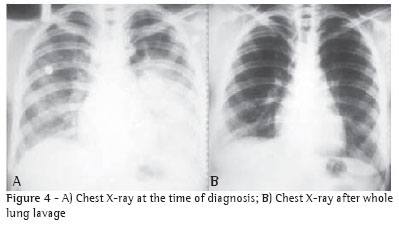

With the diagnosis confirmed, two months of pharmacological outpatient treatment was carried out at another facility. However, there was no clinical improvement; the patient presented persistent cough, pulmonary suppuration and fever. Bronchopulmonary lavage (BPL) was then proposed and was conducted initially in the right lung, since, judging from the chest X-ray, it was the most affected (Figure 4A). Pre-BPL arterial gasometry demonstrated arterial oxygen tension (PaO2) of 39mmHg, arterial carbon dioxide tension (PaCO2) of 28.7 mmHg and arterial oxygen saturation (SaO2) at 69%.

A chest X-ray (Figure 4B) indicated favorable evolution, with a virtually normal image, even in the left lung, which had not undergone lavage